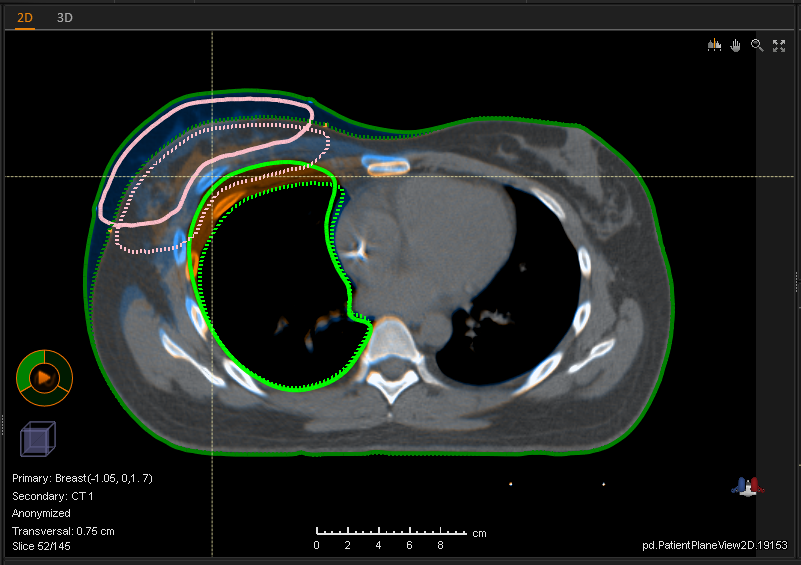

At RaySearch Laboratories, we transform energy into intelligence — enabling clinicians to harness protons, carbon ions, BNCT, and photons with greater precision, control, and adaptability.

Radiotherapy software has always been our core technology. Through advanced optimization algorithms and numerous lines of codes, our solutions shape emergent therapeutical energy into smarter, safer cancer treatments.